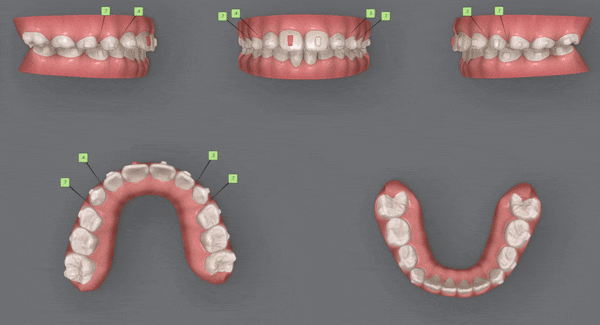

2nd Clincheck (10개)

교정기간 24/1~24/4

두번째 클린체크 는

인비절라인 10개의 장치로 이어서 진행해드렸습니다.

첫번째 클린체크에 추가적으로 어태치먼트를 부착하여

치아배열을 개선시켜 주었습니다.

어태치먼트란?

치아의 회전이나, 이동, 높이, 각도 등을 조절할 수 있는 장치로

레진을 치아에 부착해서

치아의 이동을 원하는 위치로 올바르게 배열시켜 주는

인비절라인에서 없어서는 안 될 필수 요소입니다.

3rd Clincheck (6개)

교정기간 24/4~24/7

세번째 클린체크는 6개의 인비절라인 장치를 통해

이전의 클린체크를 상호 보완, 개선 하여 마무리 해드렸습니다.